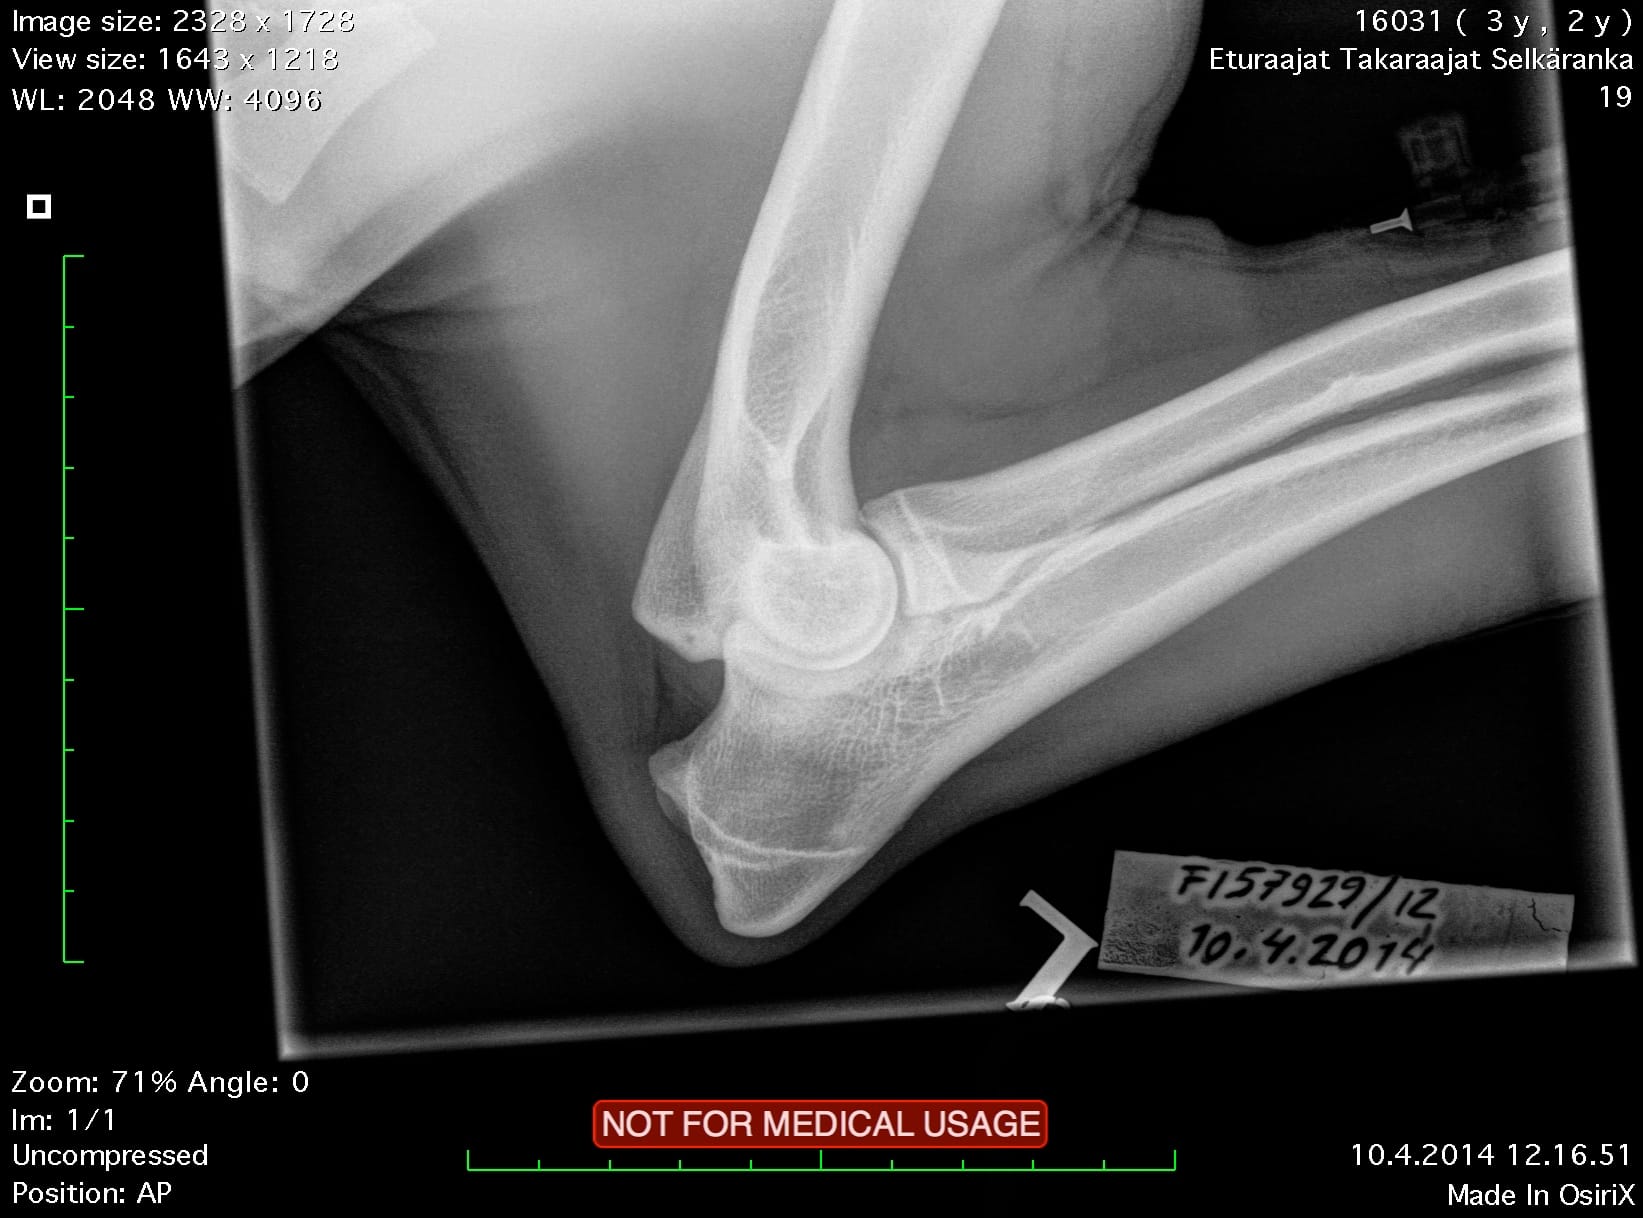

| Elbows: | 0/0 | |